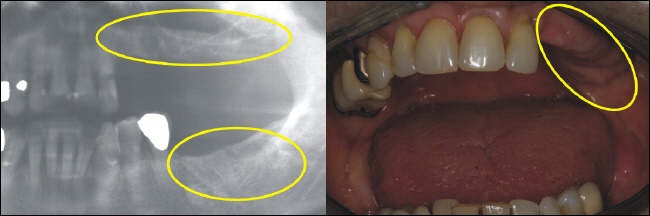

Ausgangssituation

Das Röntgenbild zeigt es (gelbe Kreise). Die gesamten Seitenzähne (Kauzähne) auf einer Seite, sowohl unten als auch oben, fehlen. Dadurch fehlt die ganze funktionell wichtige Abstützung der Kiefer zueinander.